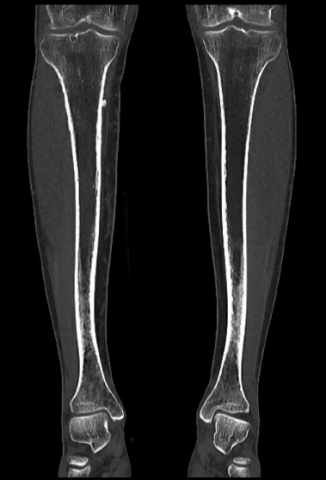

Image CT coronale epaississement.png

Image CT coronale montrant un épaississement cortical, plus marqué à droite.